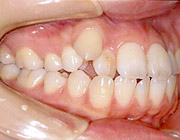

矯正治療前

矯正治療後(完成型)